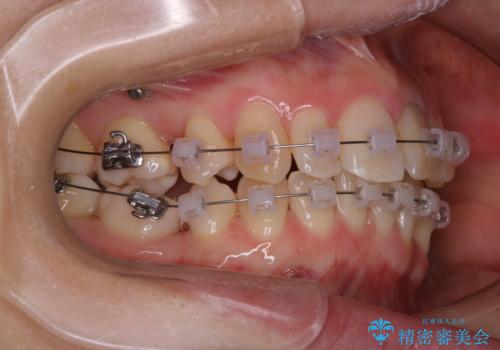

表のワイヤー矯正治療中にPMTCで綺麗に